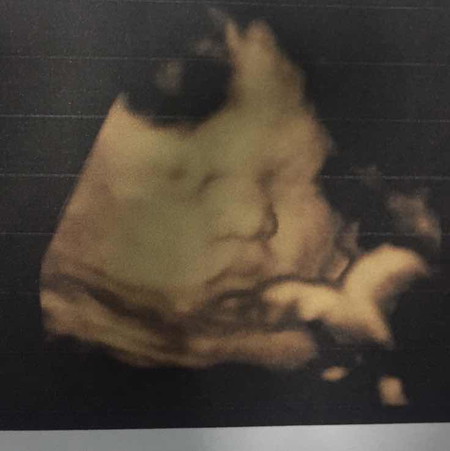

วันนี้หนูได้อายุครรภ์ 36week แล้วนะค่ะ น้ำหนักตอนนี้ 2,990g กำหนดคลอด11เมษายน2563 ค่ะ